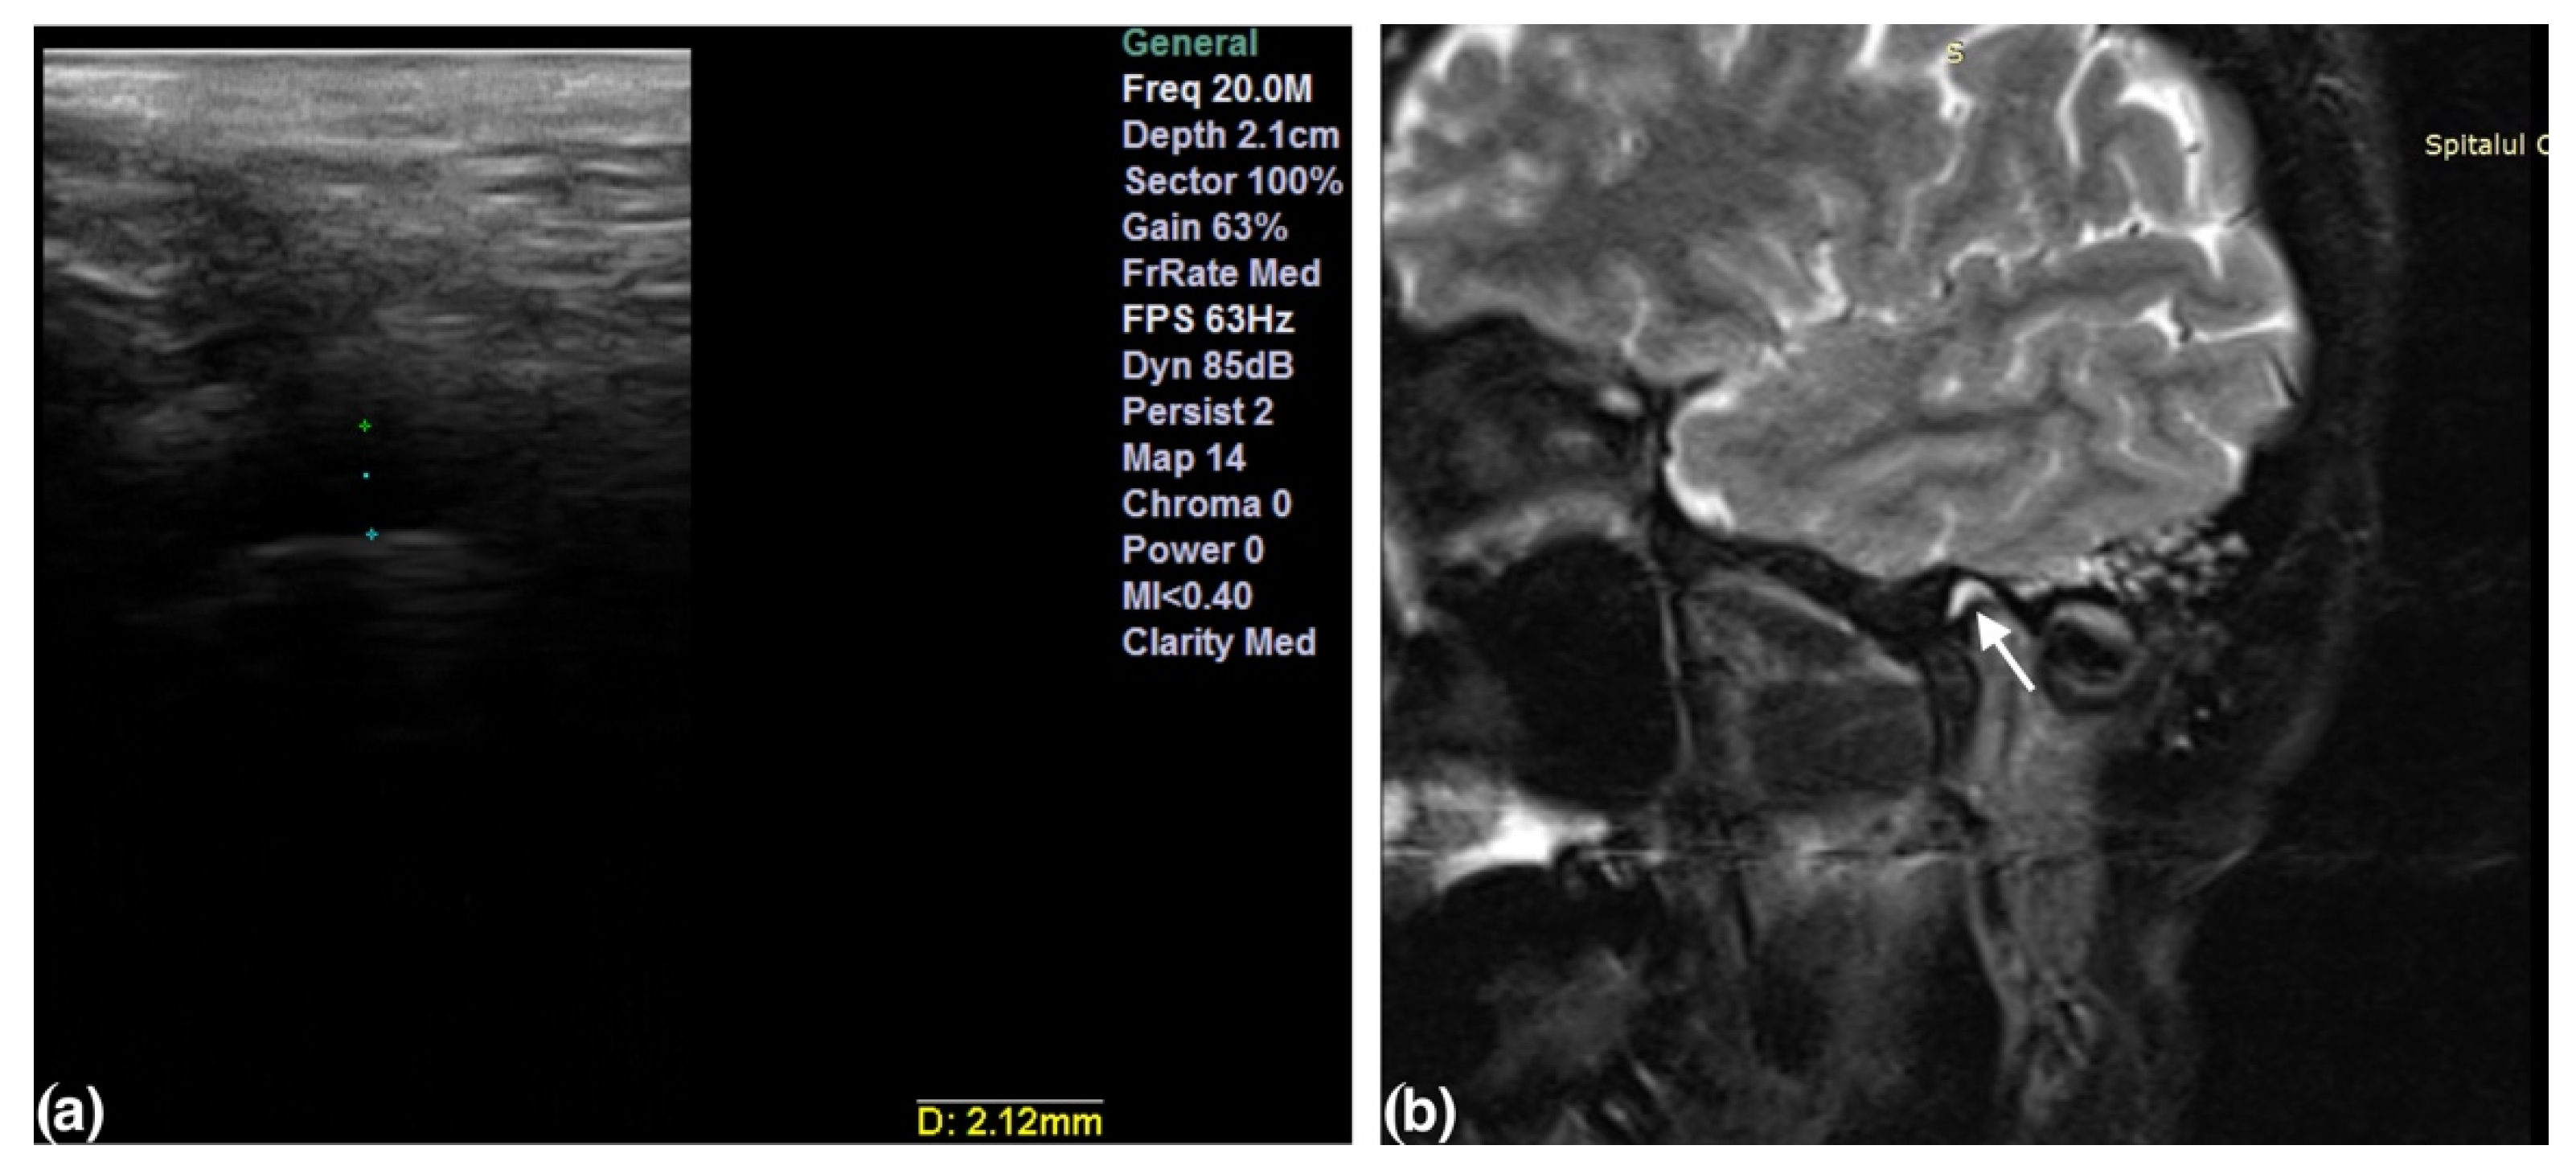

2.3. The Ultrasound Examination

- Talmaceanu, D.; Lenghel, L.M.; Bolog, N.; Stanila, R.P.; Buduru, S.; Leucuta, D.C.; Rotar, H.; Baciut, M.; Baciut, G. High-resolution ultrasonography in assessing temporomandibular joint disc position. Med. Ultrason. 2018, 20, 64–70. [Google Scholar] [CrossRef] [Green Version]

- Talmaceanu, D.; Lenghel, L.M.; Bolog, N.; Buduru, S.; Leucuta, D.; Horatiu, R. High-resolution ultrasound imaging compared to magnetic resonance imaging for temporomandibular joint disorders: An in vivo study. Eur. J. Radiol. 2020, 132, 109921. [Google Scholar] [CrossRef]

- Manfredini, D.; Tognini, F.; Melchiorre, D.; Zampa, V.; Bosco, M. Ultrasound assessment of increased capsular width as a predictor of temporomandibular joint effusion. Dentomaxillofac. Radiol. 2003, 32, 359–364. [Google Scholar] [CrossRef]

- Bas, B.; Yılmaz, N.; Gökce, E.; Akan, H. Ultrasound assessment of increased capsular width in temporomandibular joint internal derangements: Relationship with joint pain and magnetic resonance grading of joint effusion. Oral Surg. Oral Med. Oral Pathol. Oral Radiol. Endod. 2011, 112, 112–117. [Google Scholar] [CrossRef] [PubMed]